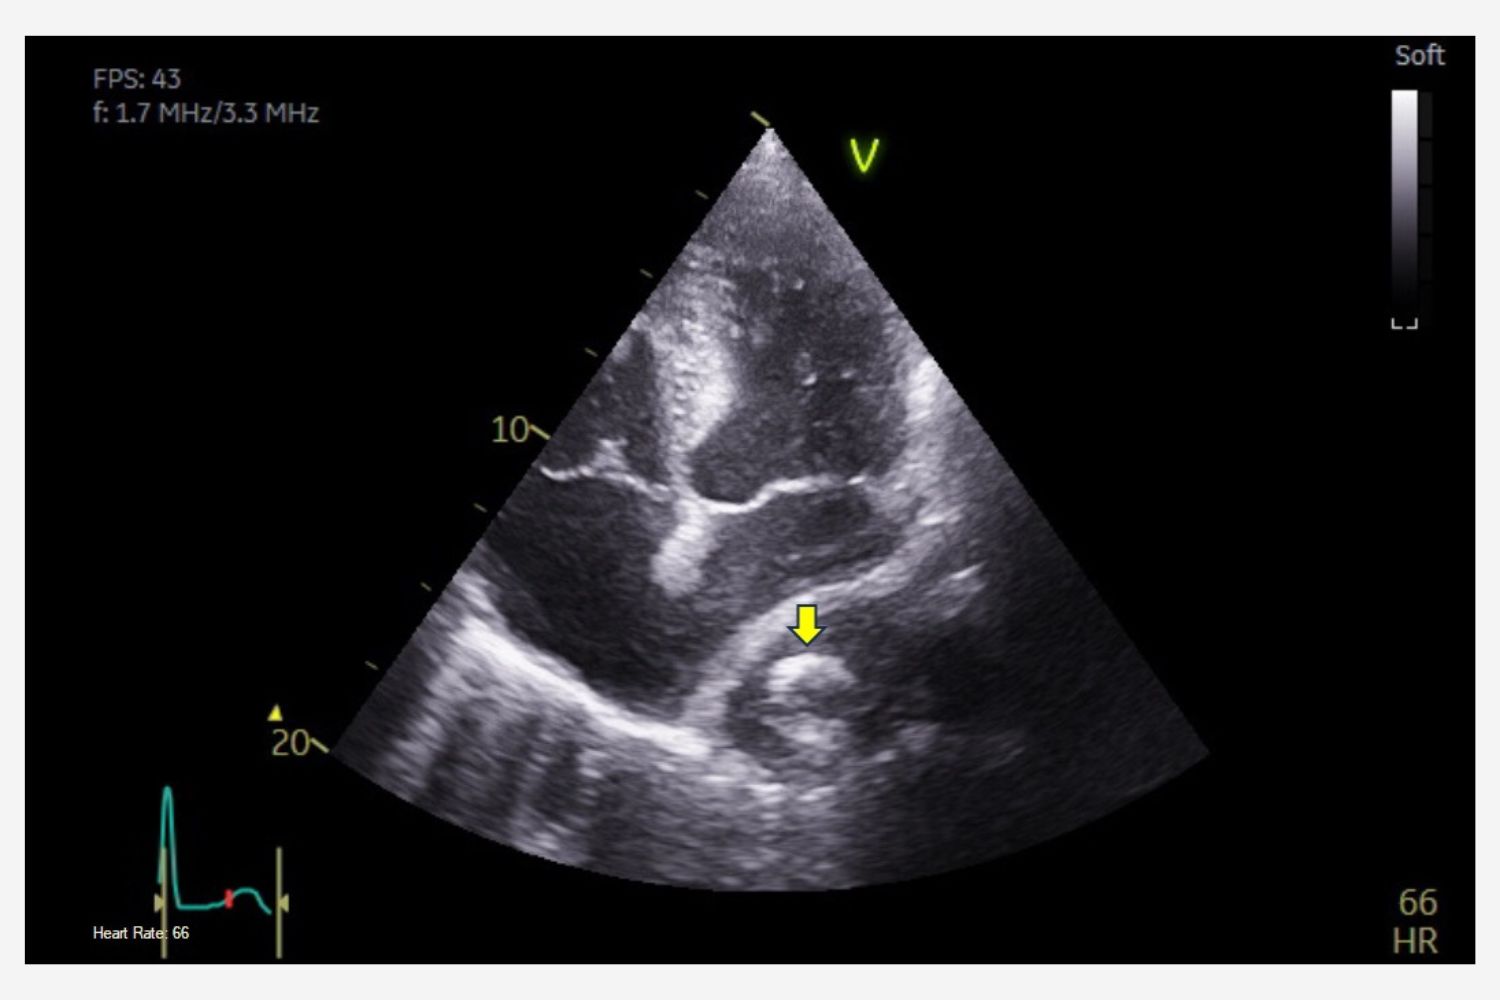

Image of the Week - 26 June 2024

Doctor Raid Faraj

Doctor Jamila Zarzur

Professor Mohamed Cherti